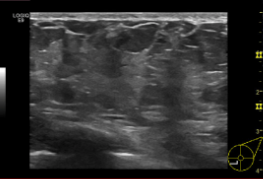

Normal breast US appearance

• Tissue

• Premammary zone (hypoechoic)

• Mammary zone (hyperechoic)

• Retromammary zone (hypoechoic)

• Pectoralis major (hyperechoic)

• Cooper’s ligament (hyperechoic bands)

• Course oblique through subcutaneous fat

• Ducts

• Collapsed (central bright echo)

• Mildly ectatic (2 hyperechoic lines, anechoic lumen)

• Severely ectatic (2 further separated hyperechoic lines)

• TDLUs

• ~2mm hypoechoic structures

• Larger with adenosis + pregnancy